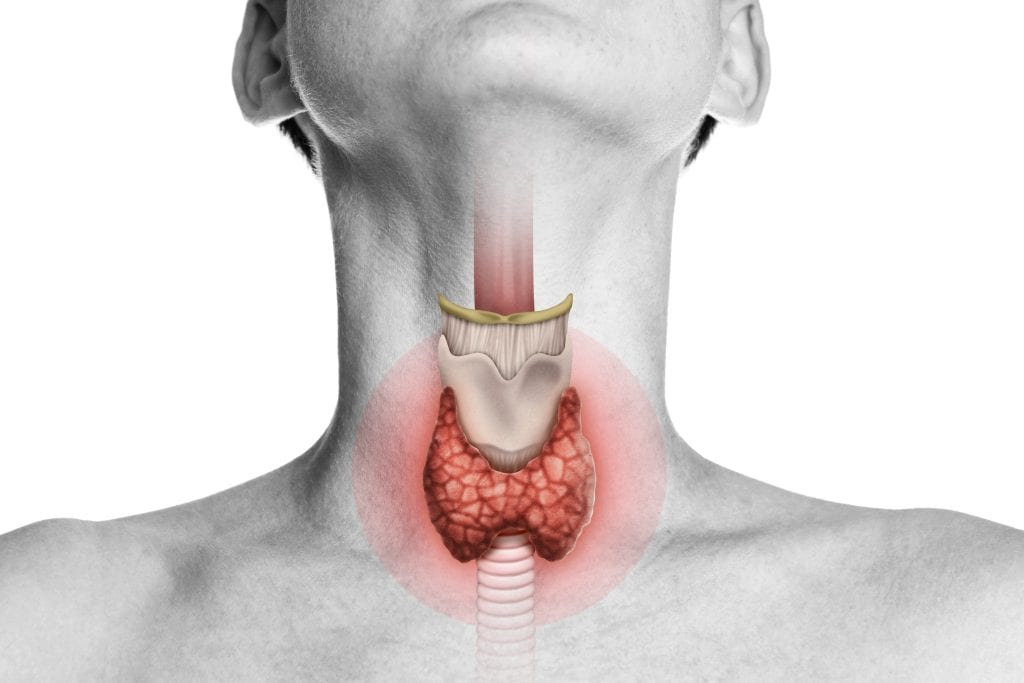

Štitnjača hipotireoza – simptomi nepravilnog rada

Štitnjača hipotireoza - bolest štitnjače

Bolest štitnjača hipotireoza je vrlo rasprostranjena u ciejlom svijetu, a predstavlja smanjenu produktivnost štitne žlijezde. Štitnjača proizvodi hormone tiroksin T4 i trijodtironin T3 koji imaju ulogu u metabolizmu svih stanica u ljudskom tijelu. Metabolizam je važan za ljudsko zdravlje jer utječe na razgradnju masti i ugljikohidrata, regulira razinu kalcija u tijelu, tjelesnu temperaturu i utječe na brzinu otkucaja srca.

Bolest štitnjača hipotireoza predstavlja poremećaj kada je smanjena proizvodnja hormona T3 i T4, pa posljedično dolazi do usporavanja metabolizma, povećanja razine kolesterola, debljanja, umora, depresija.